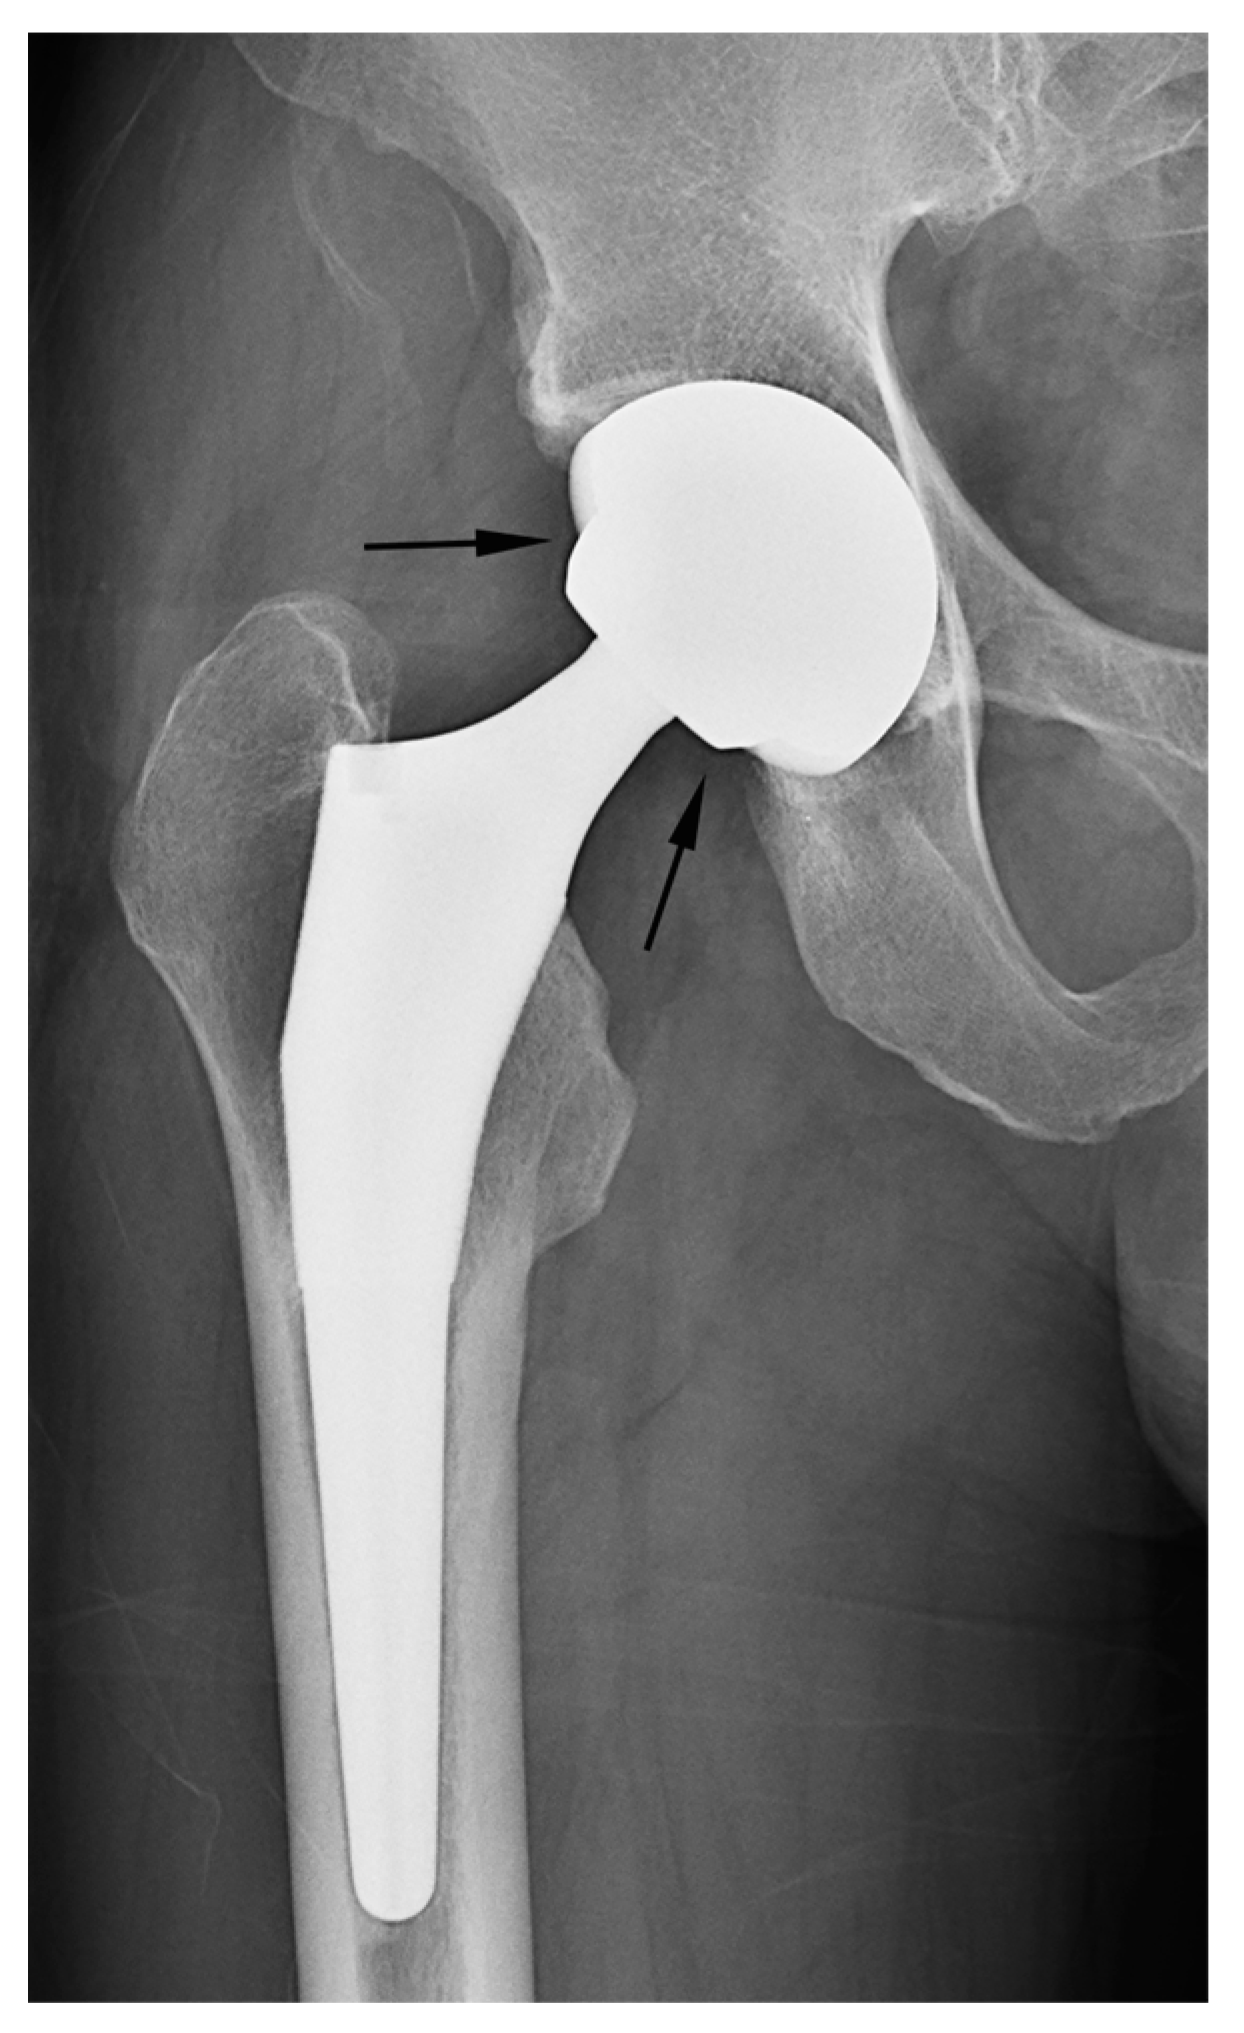

In our study, two cases of THA were erroneously classified as hemiarthroplasty based on the criterion of latitude cut deviation (Figure 7). The boundary of the artificial femoral head could be inaccurately perceived as the cup margin. Historically, femoral heads ranging from 22 mm to 28 mm in diameter have been predominantly used for THA. However, recent advancements in bearing materials have enabled the use of thinner liner designs, thereby allowing the accommodation of larger artificial femoral heads. Along with the theoretical advantages associated with larger femoral heads, this has spurred the adoption of femoral heads with diameters ranging from 36 mm to 40 mm for THA. When a sizable femoral head aligns with the anteverted acetabular cup contour, it can bewilder readers lacking familiarity with hip implants. This perplexity may lead to a misinterpretation of the cup margin and implant outline. To mitigate this confusion, adhering to the principle of drawing a chord line that links the two points where the silhouette deviates from the outer sphere contour could facilitate a precise estimation of the latitude cut.

Figure 7.

A simple radiograph after THA showing that the margin of the artificial femoral head (arrow) was confused with the margin of the cup by the raters. Adhering to the principle of determining a chord line that connects the points where the silhouette diverges from the outer sphere contour can facilitate an accurate estimation of the latitude cut.